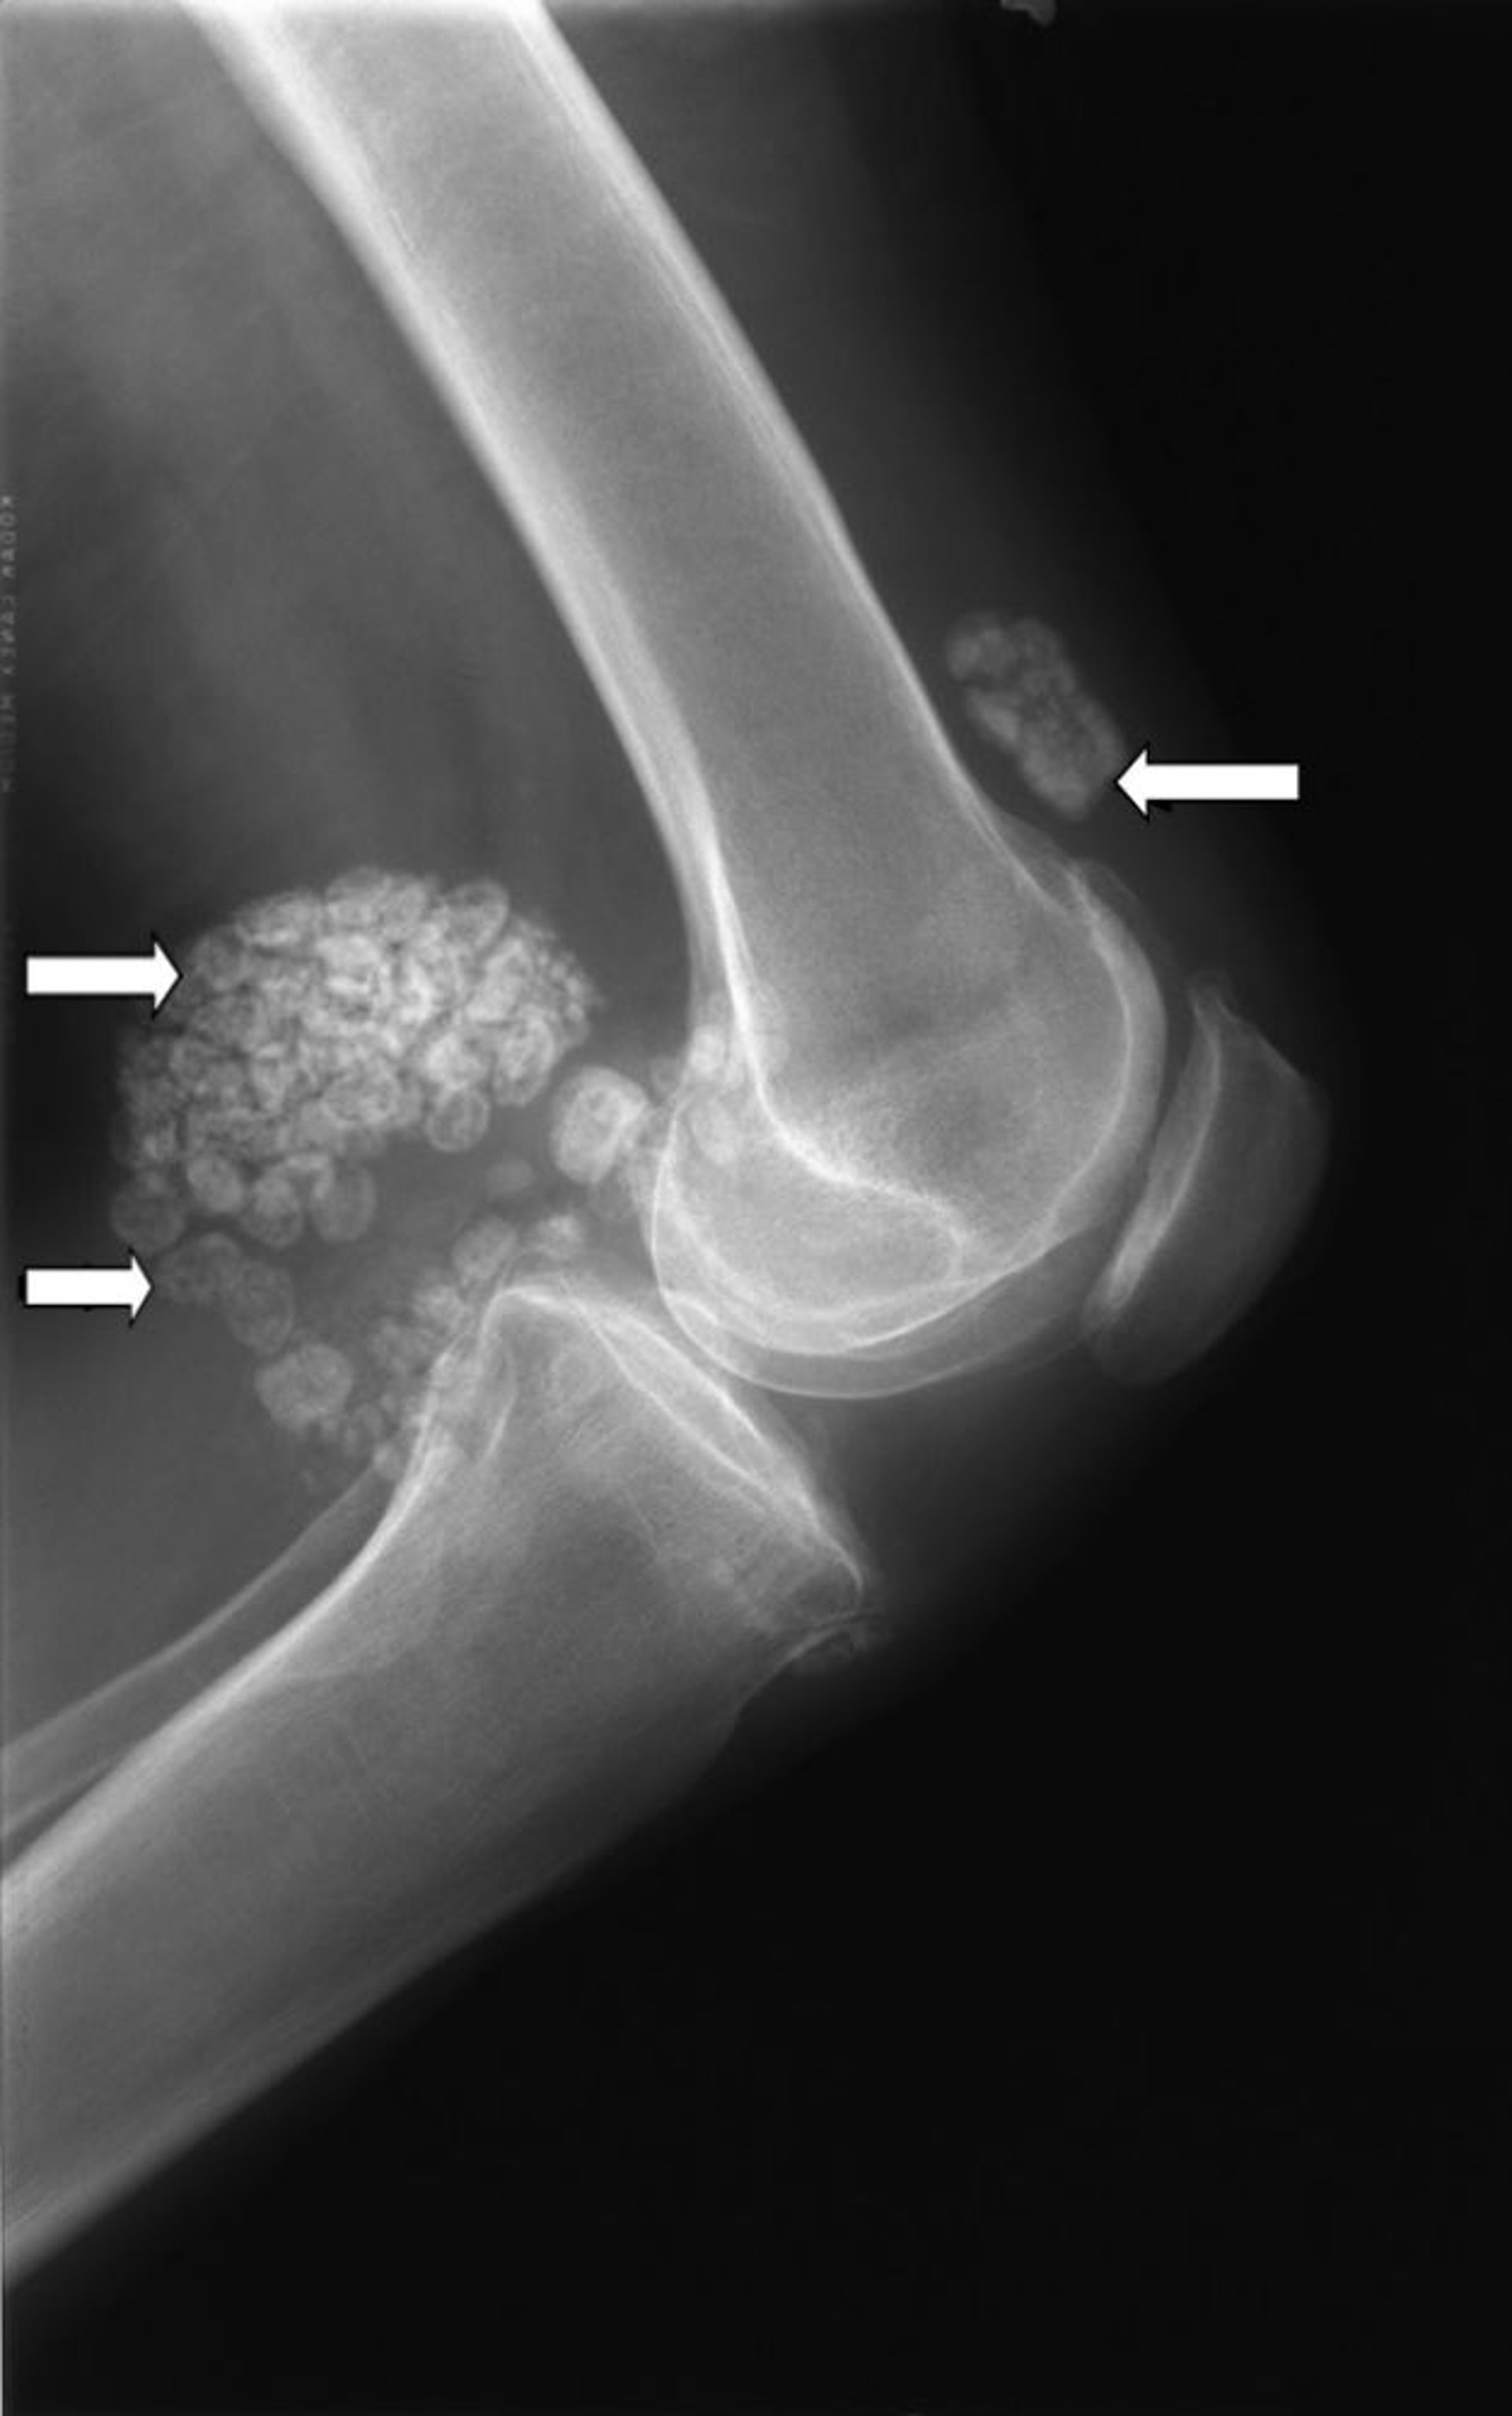

Synoviale Chondromatose

Auf dieser Röntgenaufnahme eines Knies sind mehrere Klumpen mit Knorpelgewebe zu sehen (Pfeile), wobei es sich um eine sogenannte synoviale Chondromatose handelt.

Bild mit freundlicher Genehmigung von Dr. med. Michael J. Joyce und Dr. med. Hakan Ilaslan.